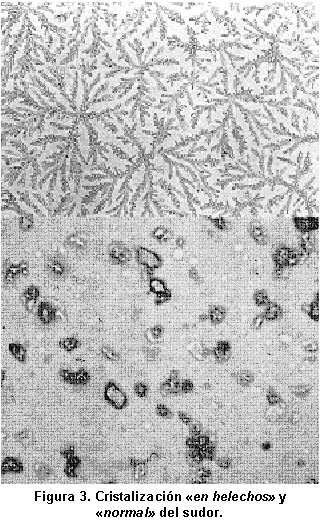

También se debe citar la prueba de desecación o cristalización del sudor, método que puede servir de gran ayuda en el diagnóstico de FQ, en aquellos casos en los que la determinación de electrólitos en sudor da valores dudosos (Cl- entre 50 y 60 mEq/l), y existe sospecha clínica de FQ.

Este método, descrito por primera vez por Kopito et al.29 en 1976 y en el que distintos grupos de investigadores hemos ido adquiriendo experiencia, con resultados positivos30,31, se basa en las formas de desecación del sudor en enfermos con FQ, que adopta formas en figuras de «helecho» o «dendritas» muy características, en contraposición con las formas «cuboides» típicas de las personas no FQ. Este es un método complementario a la determinación de electrólitos en el sudor, muy sencillo y económico de realizar en unidades de FQ con pocos medios, pero nunca debe utilizarse como método diagnóstico único, sin determinar Cl- y Na+ en sudor (Figura 3).